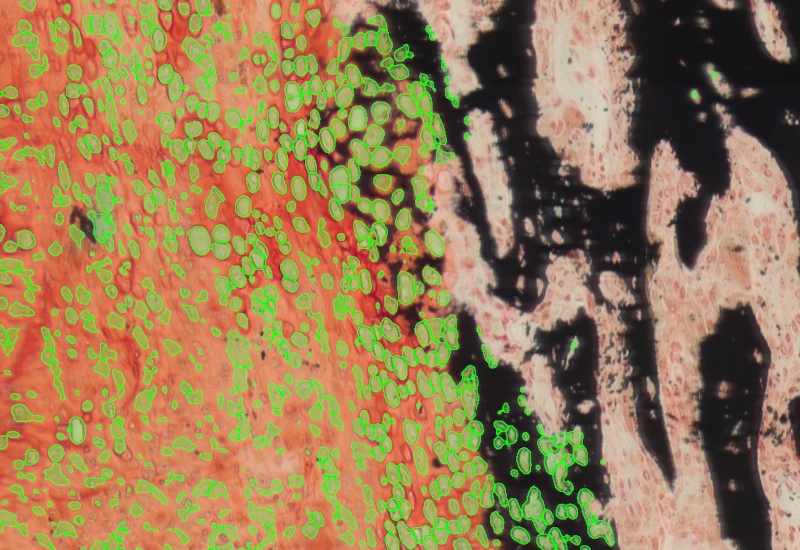

Detect megakaryocytes in IHC-stained sections, reconstruct full cell area, and quantify cell size, number of megakaryocytes containing neutrophils, and neutrophil count per megakaryocyte.

The IHC Megakaryocytes App allows for detection of megakaryocytes based on specific marker staining. It outputs number and size of detected megakaryocytes as well as the number of megakaryocytes that contain neutrophils inside their cytoplasm and the number of neutrophils inside each megakaryocyte.

Megakaryocyte identification